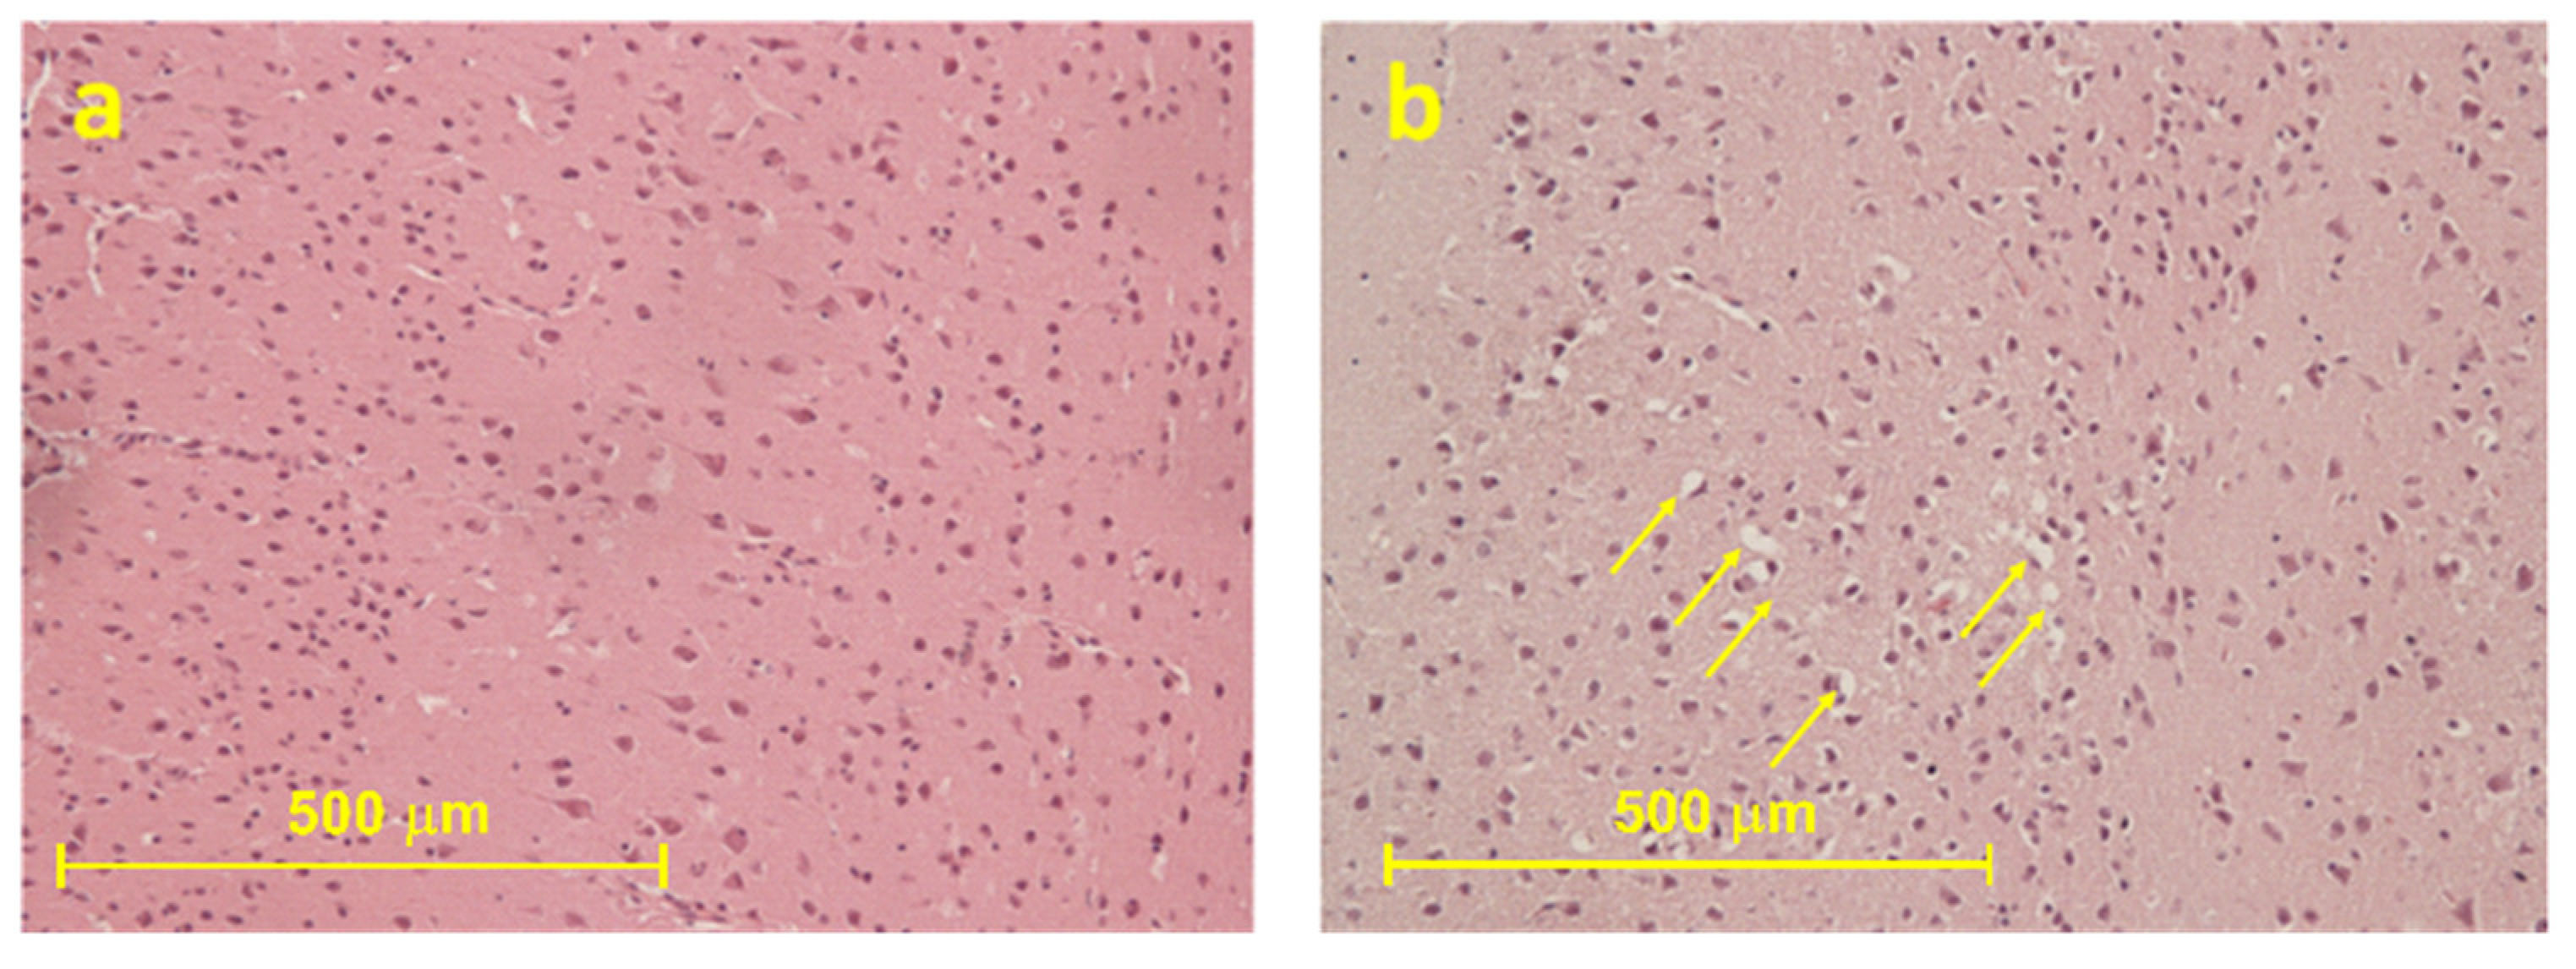

2.2.1. Histological Results

2.2.2. Immunohistochemical Results